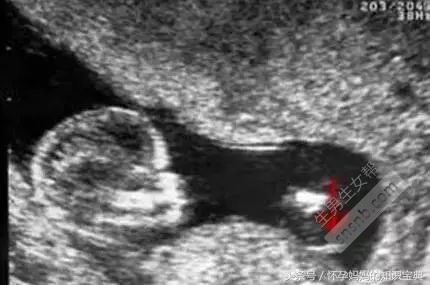

B超图分辨男宝女宝性器官

在照B超的时候,医生都会从屁股底下照看看左右的大腿,仔细观察的话可以发现在图中会有“谜之小凸起”,上图中的箭头所指就是,看到这里相信不用我说各位也一定看出来是一位小王子了。